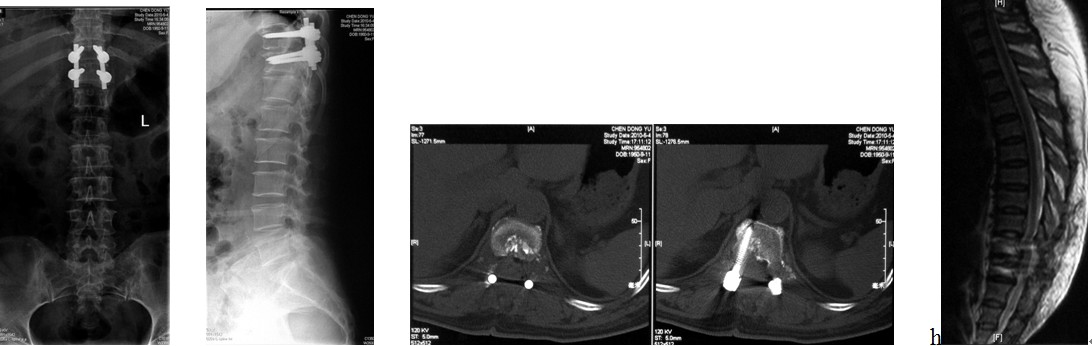

4. 典型病例:病例1,患者男性,40岁,司机。主因胸腰背部疼痛3年,肛周麻木、性功能减退并伴双足下垂2年,症状加重且二便肥力、无法工作1年入院。入院查体:一般情况良好,体胖、体重105kg。步态不稳,步行缓慢。胸腰段脊柱背部轻压痛,无放射。双侧股四头肌力IV级,双侧胫前肌力I级,双侧足下垂。鞍区感觉减退,无病理征。双侧跟、膝腱反射消失。血化验检查正常。X线平片显示T12~L1椎间隙明显变窄。CT显示T12~L1椎间盘突出并椎体后缘离断。MRI显示T12~L1椎间盘呈中央型突出,椎管狭窄,脊髓明显受压变形。入院诊断:T12~L1椎间盘突出症伴椎体后缘离断,马尾神经损害。术前检查完成后,在气管插管全麻下行上述经极外侧入路T12~L1椎间盘切除手术治疗,整个手术过程顺利,无术中及术后并发症发生,术后1周顺利出院。出院时,其双侧股四头肌、胫前肌肌力已分别恢复至V级和III级;鞍区感觉减退亦有明显好转。术后显示T12~L1突出之椎间盘及离断之椎体后缘已被完全切除,椎间融合器及椎弓根螺钉位置佳,脊柱局部生理曲度良好(图2a~2l)。病例2,女性患者,59岁。主因间歇性跛行,双下肢无力3年入院。入院诊断:T11椎体后上缘骨软骨瘤。以与病例1相同的术式行椎体骨软骨瘤的彻底切除(图3a~3l),无手术并发症发生,术后患者下肢症状明显改善。

图3a~3d. 典型病例2患者术前均显示为T11椎体后上缘骨软骨瘤,分明显突入椎管, 脊髓明显受压.

图3e~3h.典型病历2术中椎管后壁切除及极外侧显露情况

图3i~3l. 典型病例2患者术后之线片, CT, MRI显示骨软骨瘤已被彻底切除, 脊髓获得充分减压, 内固定位置良好.